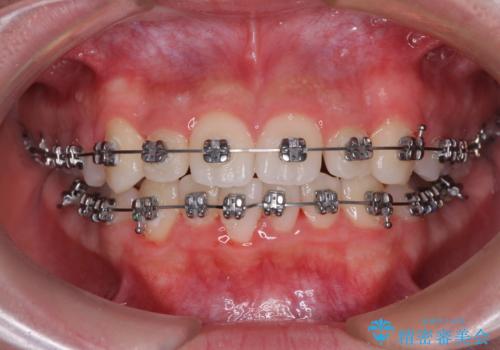

- メタルブラケット

- 治療期間

- 11ヶ月

叢生のため磨き残しの多い歯列でしたが、1年弱で治療を終了でき、磨き残しや歯肉の腫れが著しく改善されました。